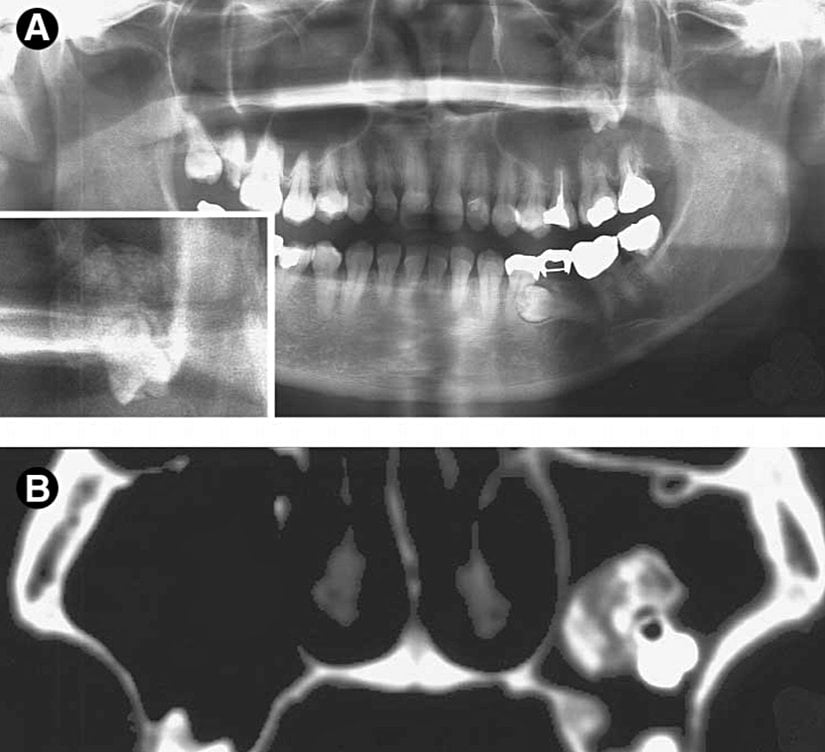

Dışarıdan bakıldığında diş gözükmese bile radyografik ve histopatolojik incelemelerde dişe rastlanılan bir vaka. “Teratom”un nadir bir çeşidini gördüğümüz bu vakada, totipotent hücrelerin diş benzeri hücrelere farklılaşmış olduğunu anlıyoruz.